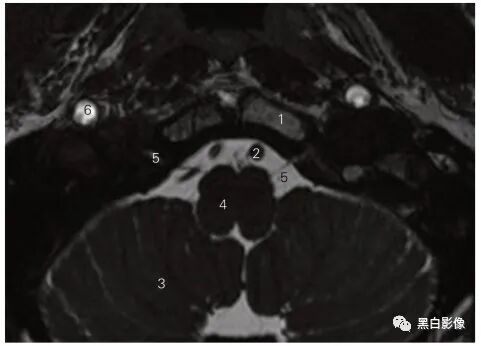

图5-6 经三叉神经的横断层MR T2加权图像

1 颞上回 superior temporal gyrus 2 杏仁体 amygdaloid body

3 颞中回 middle temporal gyrus 4 颞下回 inferior temporal gyrus

5 三叉神经 trigeminal nerve 6 脑桥 pons

7 小脑半球 cerebellar hemisphere 8 第四脑室 fourth ventricle

9 脑桥小脑角池 cistern of pontocerebellar trigone

10 三叉神经节 trigeminal ganglion 11 基底动脉 basilar artery

12 动眼神经 oculomotor nerve